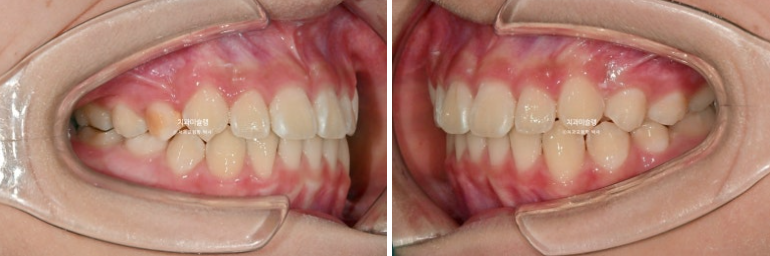

이제 전 후 비교 볼게요

23.10~25.11

과개교합과 중심선 불일치의 개선

완성된 교합은 1급 교합관계를 보입니다.

나중에 성인이 되어 2차교정을 안해도 될 정도의 완성도 입니다.